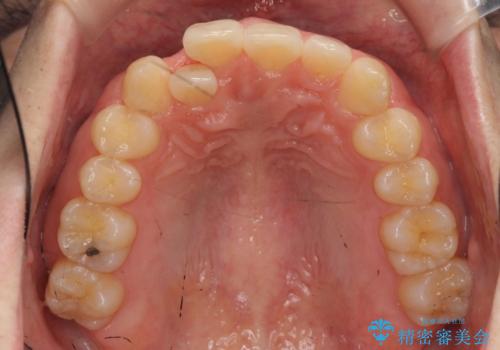

- 右上の前歯が内側に入っているのを気にして来院。

右上の奥歯を後ろに移動して、前に出すスペースを確保してから並べました。

奥歯を後ろに送るために、矯正用インプラントを使用しています。